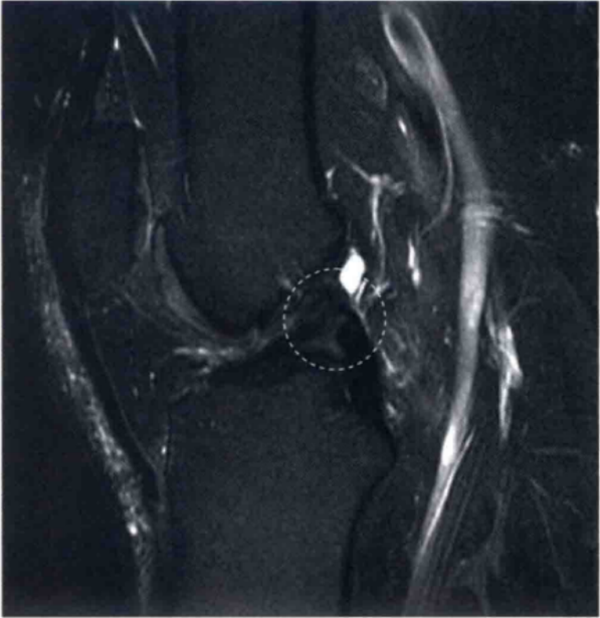

图1 a和b分别显示的是在T2图像中矢状位和轴位正常的ACL。

a显示绷紧,可见明显的ACL低信号(白色箭头)。在a中也显示正常的胫骨附着点(圆形标记)。b显示在水平面上正常的股骨附着点